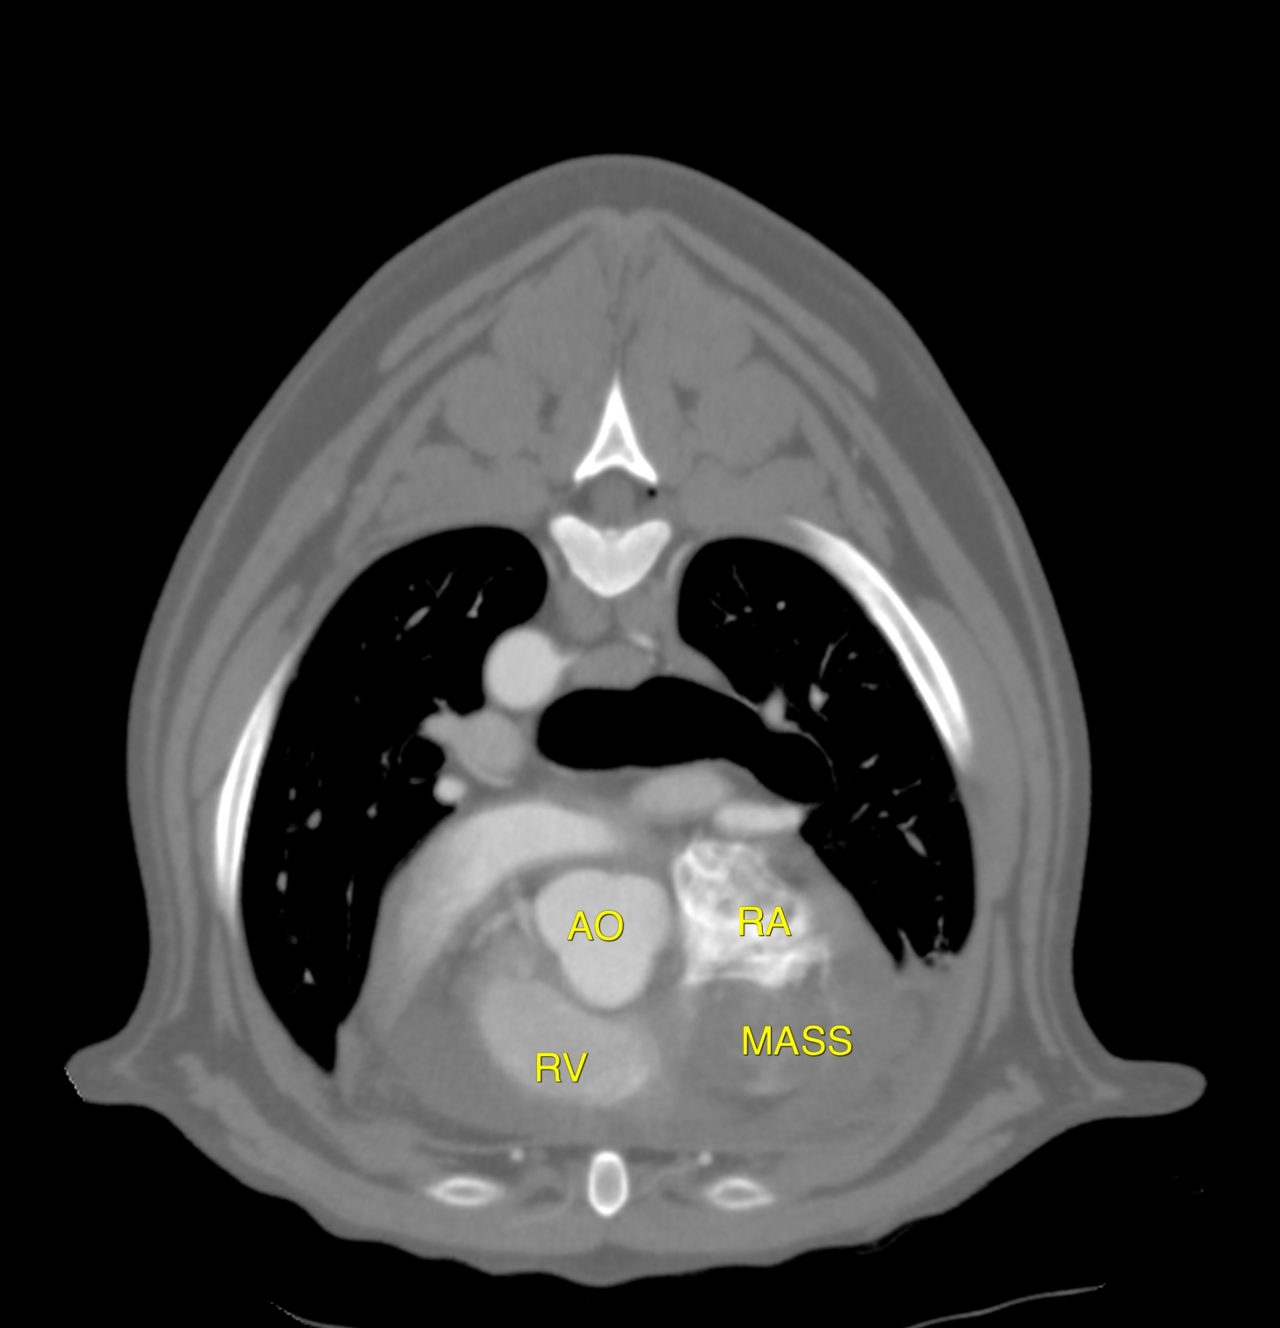

ゴールデンレトリバーは血管肉腫の好発犬種です。特に右心耳、肝臓、脾臓などに発生する事が知られています。右心耳であれば心タンポナーデという状態を引き起こし、循環状態が悪化し低血圧となり突然倒れてしまいます。聴診でマッフルサウンド、心電図では電気的交互脈、胸部エックス線ではムーンハートを呈しています。超音波で拡張期に右心房が虚脱する様子が確認されます。心嚢内圧を下げるために、直ちに心膜穿刺術で救命を行います。残念ながらこの腫瘍に対する根治的な治療方法はなく、進行すれば再発性の出血性心タンポナーデを何度も繰り返す(何度も倒れる)ことになります。そこで、姑息的な手段ですが心膜切除術を行なっておけば心タンポナーデを回避する事が出来ます。近年、テクノロジーの発展とともに開胸術ではなく胸腔鏡を使って小さな傷で手術を行う事が可能となっています。この病気は突然ワンコを襲い、見つかった時はすでに進行している事がほとんどです。だからこそ、最小侵襲で最大の効果が期待できる胸腔鏡下心膜切除術に真の価値があると言えます。開胸術に比べ痛みも少なく入院も短くて済むからです。我々はたとえ根治不能な病気であっても、患者さんがQOLを保ちながらご家族との大切な時間を1日でも長く過ごせるように、チームで話し合いながら”より良い”を常に模索し続けます。